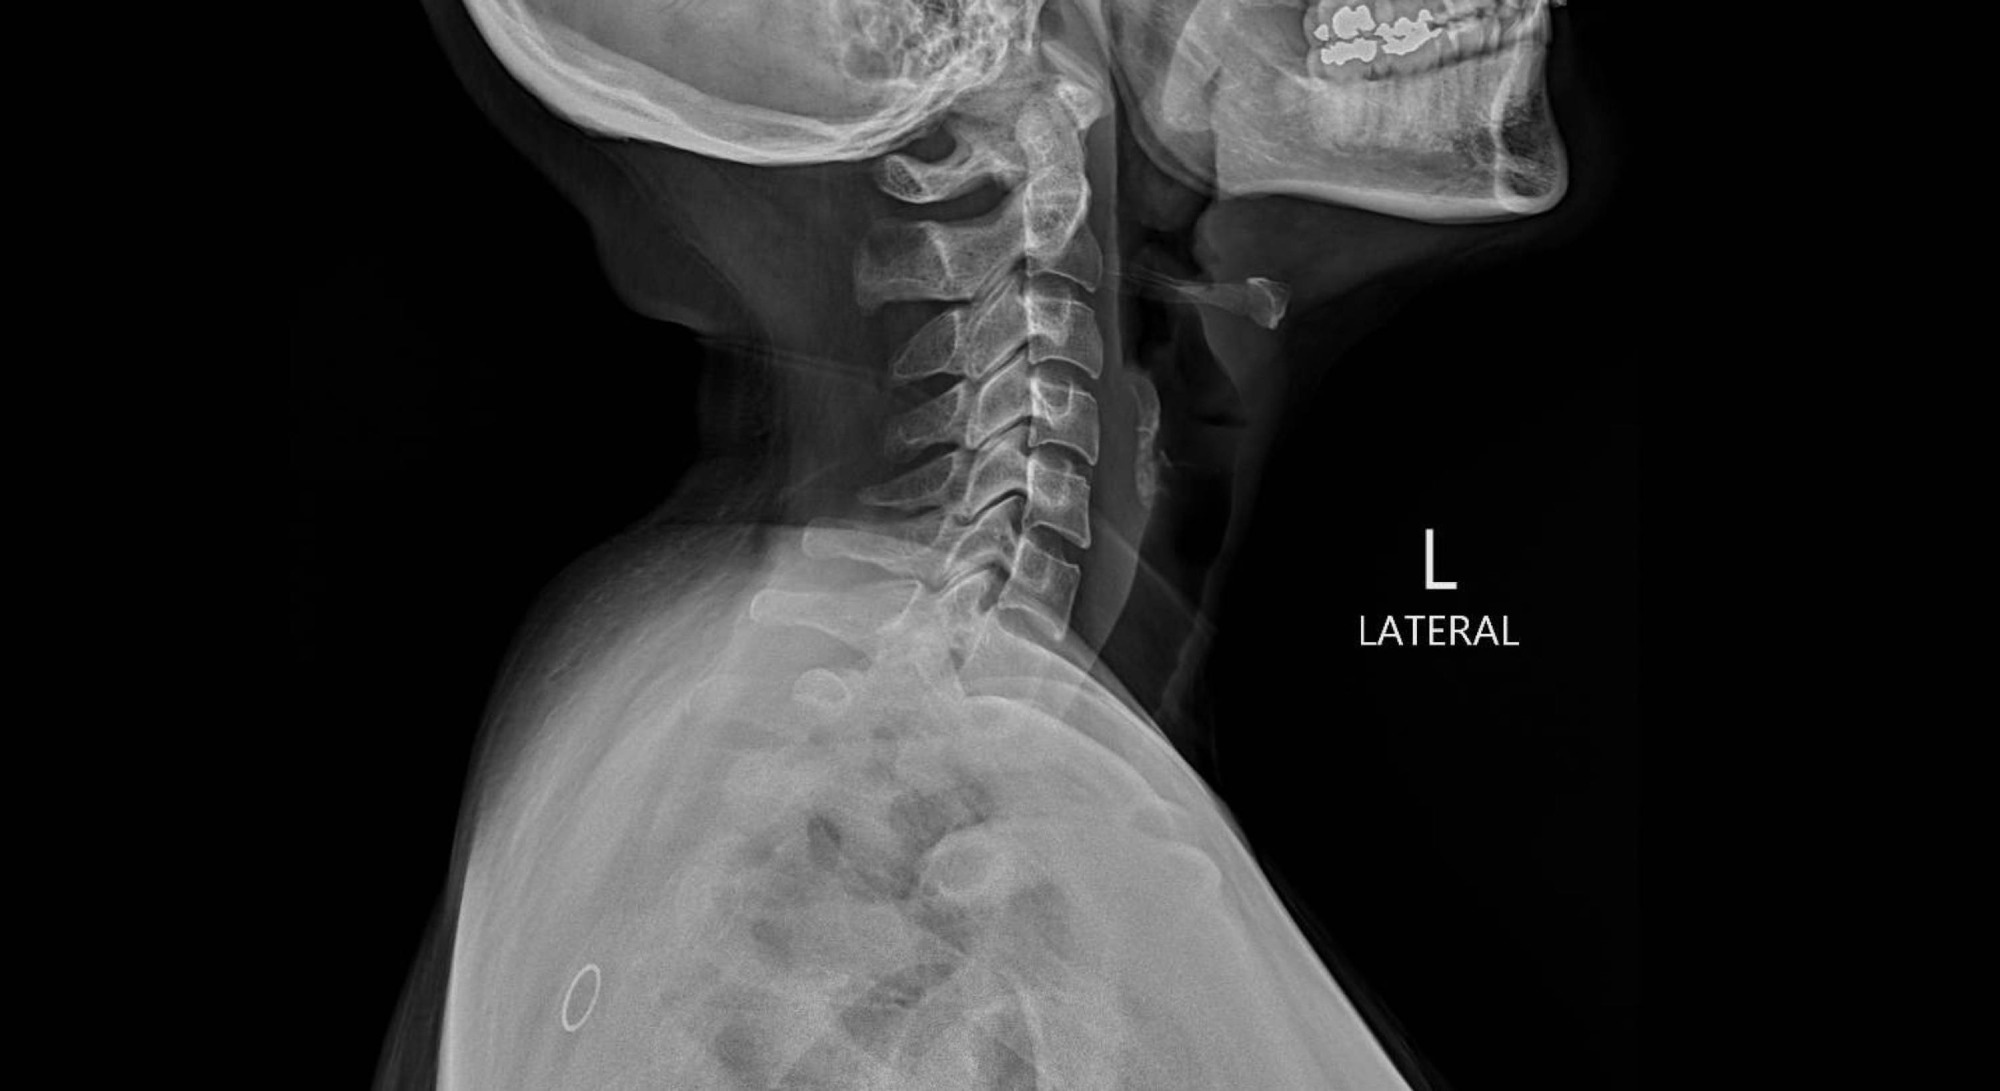

Study: The Rise of Deepfake Medical Imaging: Radiologists’ Diagnostic Accuracy in Detecting ChatGPT-generated Radiographs. Image Credit: Peter Porrini / Shutterstock

Dataset 1 comprised 77 real radiographs and 77 synthetic images generated by GPT-4o. Synthetic images included radiographs of the chest, extremities, and spine. Real images were obtained from a local database and publicly available datasets.

Uniform noise or grain, a subtly unnatural soft-tissue texture, symmetric vertebral alignment, overly smooth bones, altered bone shape, and the absence of normal anatomical irregularities were reported by radiologists as some of the most distinctive features of AI-generated radiographs. Fracture lines were reported to be unusually clean, consistent, and smooth in AI-generated radiographs.